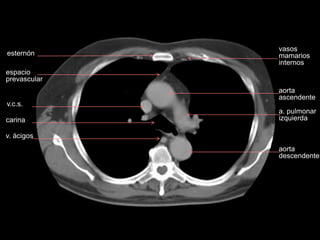

esternón

v.c.s.

carina

v. ácigos

espacio

prevascular

aorta

ascendente

a. pulmonar

izquierda

descendente

vasos

mamarios

internos